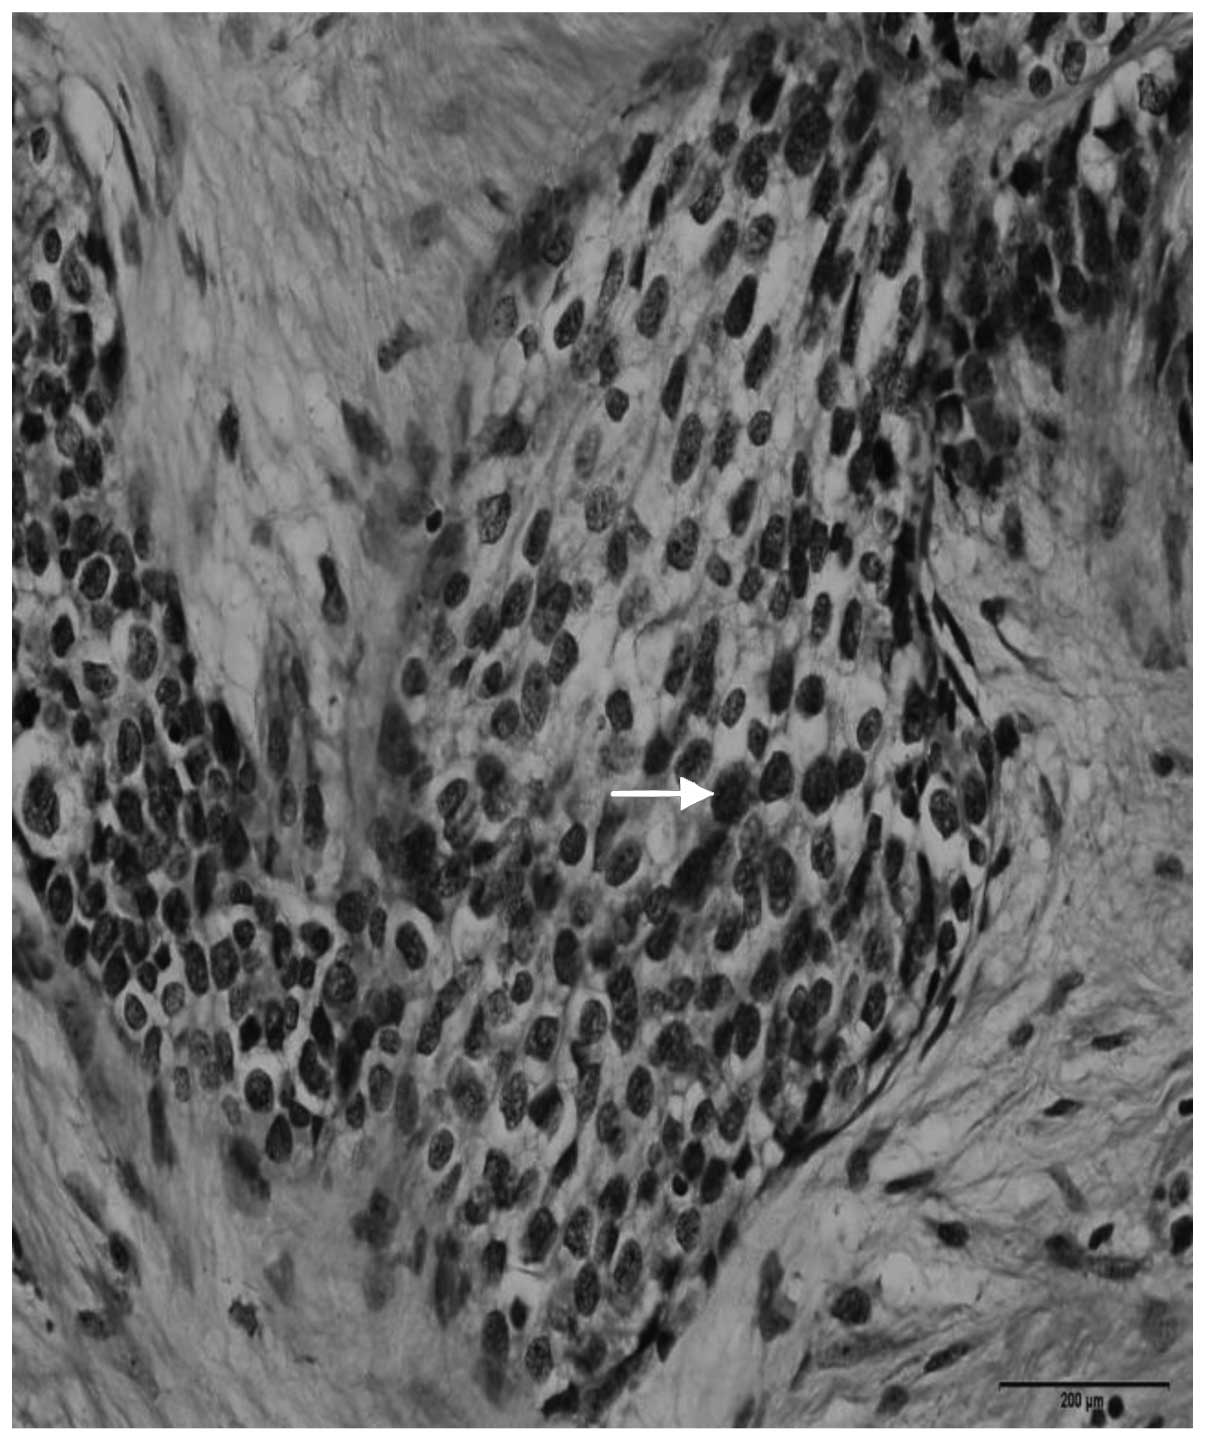

Computed tomography (CT) scans of the abdomen and pelvis revealed a heterogeneous, hypovascular pelvic mass measuring 7.6×6.8 cm (Fig. 1). The mass was located posteriorly and superiorly to the bladder, with thickening of the rectum and a right large hydronephrosis (Fig. 2). Additionally, colonoscopy identified extrinsic compression into the rectum. The differential diagnosis was of a lymphoproliferative lesion or retroperitoneal sarcoma. However, subsequent ultrasound-guided biopsy and histopathological analysis of the pelvic mass indicated a morphology compatible with a high-grade malignant neoplasm. It was characterized by groups of small cells featuring large and hyperchromatic nuclei with scant cytoplasm, arranged in the desmoplastic stroma. Immunohistochemical analysis of this sample revealed positivity for cytokeratin (monoclonal mouse anti-human; clone, AE1/AE3) and desmin (monoclonal mouse anti-human; clone, D33), and negativity for S100 protein (polyclonal rabbit anti-S-100), CD45 (leucocyte common antigen; monoclonal mouse anti-human; clone, 2D1), myogenin (monoclonal mouse anti-myogenin; clone, F5D), chromogranin (polyclonal rabbit anti-human) and WT-1 (Wilms' tumor suppressor gene 1; monoclonal mouse anti-human; clone, 6FH2; all purchased from Dako North America, Inc., Carpinteria, CA, USA). The CD45 negativity excluded a diagnosis of lymphoma. These morphological and immunohistochemical findings indicated a diagnosis of DSRCT (World Health Organization classification, 2013) (7).

Analysis of the surgical specimen confirmed the diagnosis of DSRCT. The morphological and immunohistochemical findings were identical to those observed in the first biopsy. Histological sections indicated a high-grade malignant neoplasm, represented by small cells with hyperchromic nuclei in the center of desmoplastic stroma (Fig. 5). Furthermore, immunohistochemical analysis identified positivity for cytokeratin and desmin, and negativity for S-100, myogenin, Wilms' tumor suppressor gene 1 (WT1), cluster of differentiation 45 (CD45) and chromogranin antibodies. The CD45 negativity excluded a diagnosis of lymphoma.